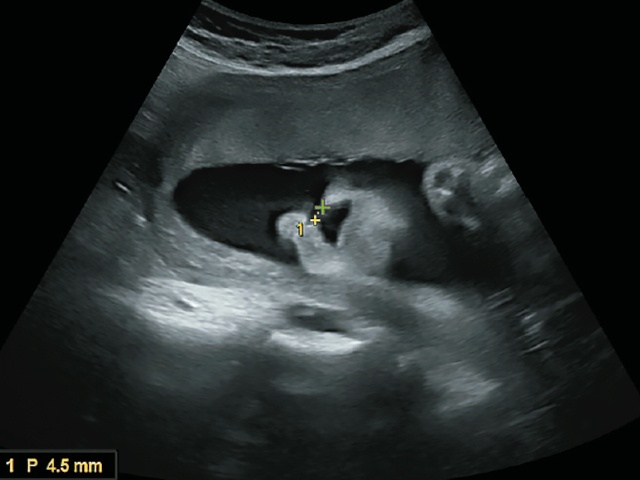

При динамическом наблюдении данного случая в 27 нед беременности определяется увеличение ширины дефекта до 4,5 мм. Визуализируется деформация крыла носа (рис. 13-17).

Рис. 13. Ширина дефекта 4,5 мм. 27 нед беременности.

Рис. 14. Большая правосторонняя расщелина губы и нёба (стрелка).